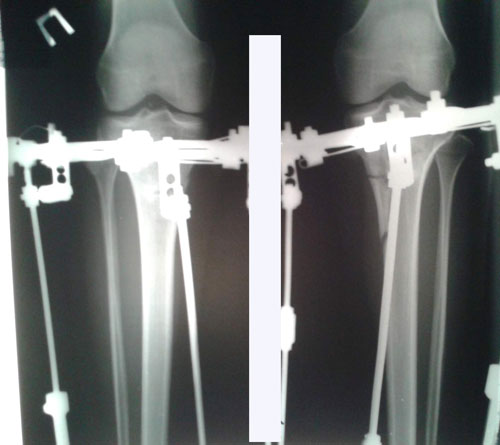

Поздравляю! Ура! Результат отличный!Sekretar Onipko писал(а):Рентген в 58 дней.

Сращение отличное, через неделю снимаем аппараты.